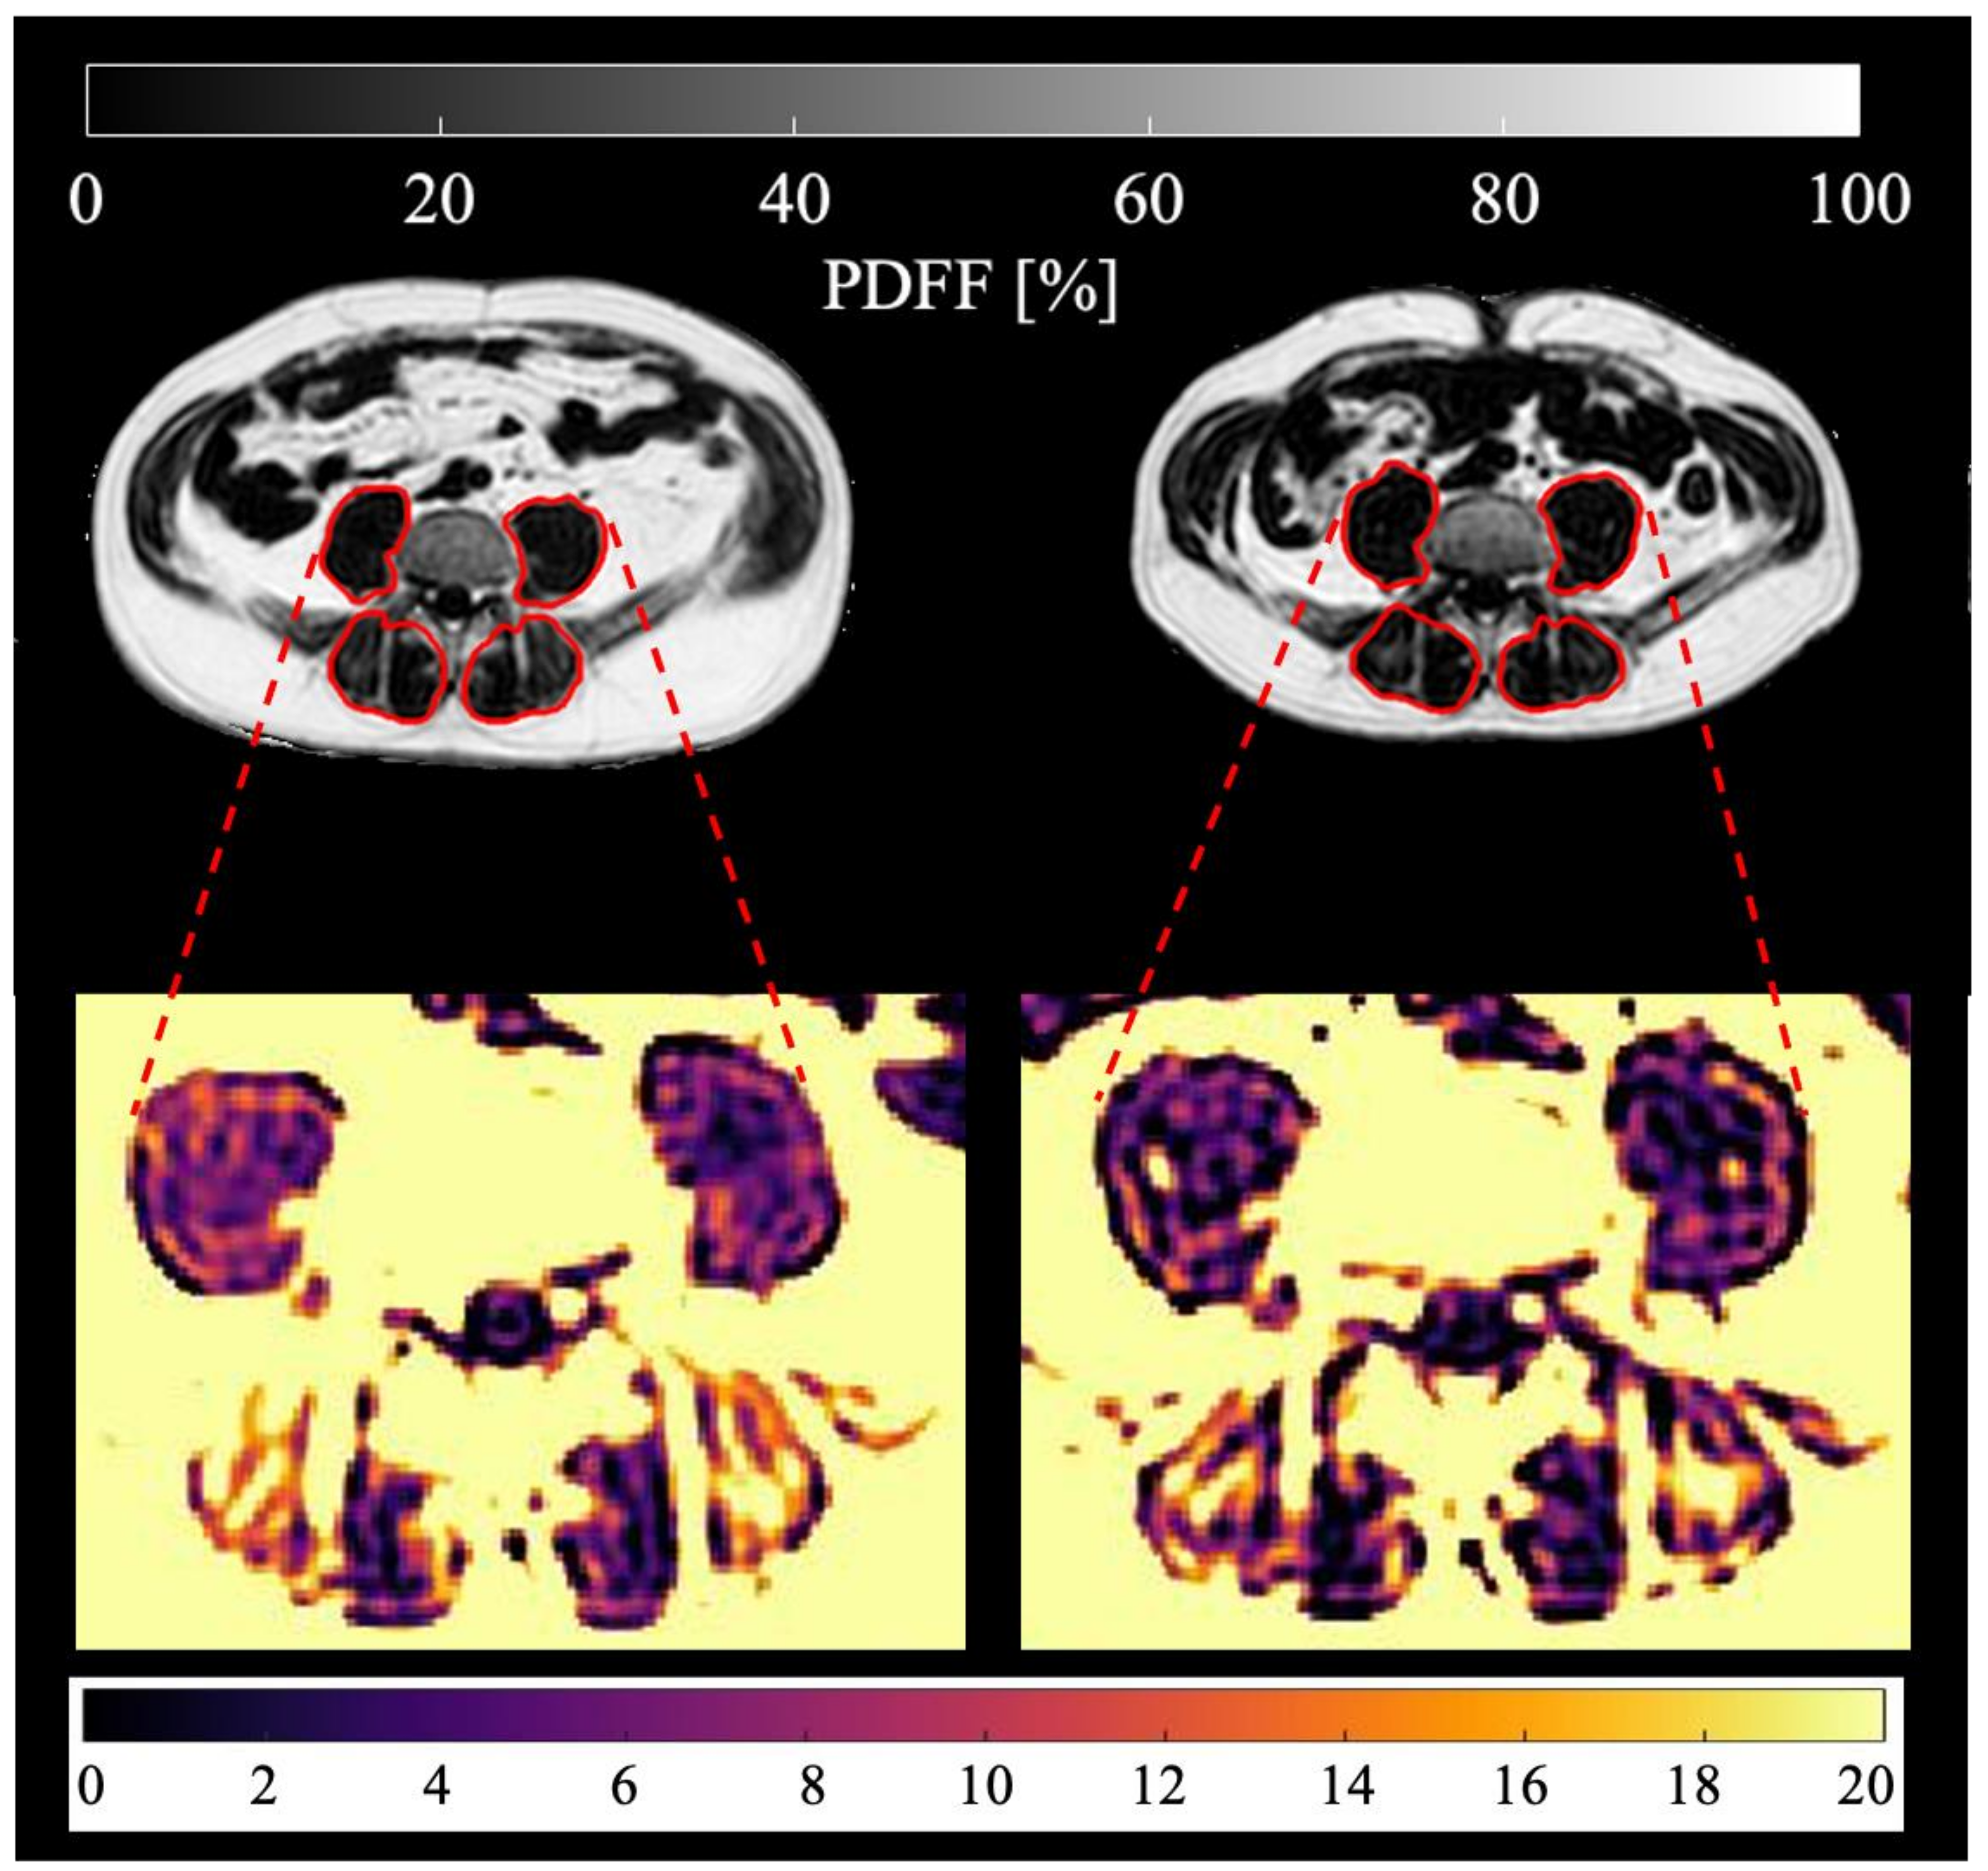

Figure 2.

Representative PDFF maps of the psoas and erector spinae muscles (marked in red) of the same patient (male, 56 years old, BMI at baseline 28.6 kg/m2, BMI at follow-up 24.2 kg/m2, suffering from adenocarcinoma of the esophagogastric junction) are shown. Baseline scan is on the left, third follow-up scan after 218 days on the right. Mean psoas PDFF at baseline: 12.02%, mean erector spinae PDFF at baseline: 16.69%, mean psoas PDFF at follow-up: 8.62%, mean erector spinae PDFF at follow-up: 14.85%.